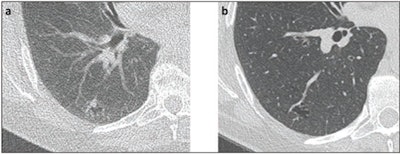

Lung nodules found on screening CT are categorized using the Lung-RADS system or categories generated by the Dutch-Belgian Randomized Lung Cancer Screening (NELSON) trial. But nodules identified on follow-up screening may require a different approach than those found on baseline CT because they may have a higher risk of malignancy, the authors noted.

Nodule assessment algorithms such as those from the Fleischner Society and the NELSON trial use the same size cutoffs for new lung nodules on follow-up CT. But the Lung-RADS protocol recommends a lower size threshold (with the "clinical," or standard protocol setting the size for a suspicious nodule at ≥ 8 to < 15 mm and the stricter protocol setting it at 6 to > 8 mm).

Byrne and Hammer investigated the utility of both Lung-RADS algorithms for assessing new nodules found on follow-up CT. Their study included 185 follow-up CT lung cancer screening exams with nodules in 185 patients with available baseline exams. Of these 185 nodules, 56% were existing and 44% were new, with a median diameter of 7 mm; they were classified in the following Lung-RAD categories: